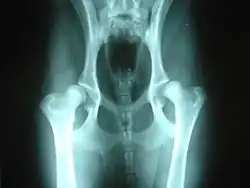

La gravedad de la displasia se puede medir si trazamos el denominado ángulo de Norberg. Éste consiste en trazar sobre una radiografía una línea que vaya desde el centro de una cabeza del fémur, al centro de la otra. Posteriormente, desde ambos extremos se traza otra línea que pase por el borde acetabular dorsal, formando así un ángulo con la anterior. Según la amplitud del ángulo, tenemos que:

- No se presenta displasia si es mayor de 105.º.

- Si mide entre 100°-105.º, el animal tiene displasia leve.

- Si mide entre 90°-100º, la displasia es moderada. Se acompaña de enfermedad degenerativa articular y aplanamiento del acetábulo.

- Si mide menos de 90°, la displasia es grave. Puede llegar a presentar luxación.